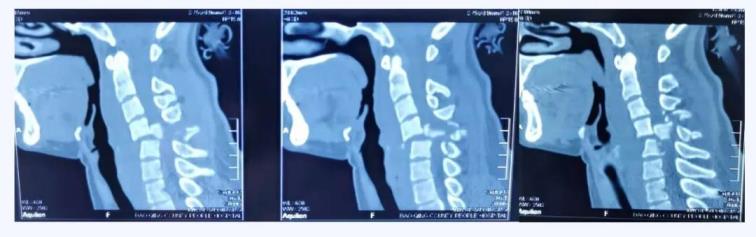

術(shù)前CT

經(jīng)查,病人確診為“頸椎骨折脫位 、頸髓高位損傷四肢癱”,以致四肢感覺運(yùn)動(dòng)均喪失。第五頸椎椎體完全脫位于后方椎管內(nèi),頸脊髓損傷嚴(yán)重,這類損傷導(dǎo)致脊髓水腫向上蔓延,可殃及呼吸循環(huán)控制中樞,患者隨時(shí)都有呼吸循環(huán)驟停危及生命的風(fēng)險(xiǎn)。我院骨科首席專家、業(yè)務(wù)院長喬建民教授聞?dòng)嵹s到醫(yī)院進(jìn)行緊急救治。一般的頸椎骨折脫位,只需將脫位的椎體復(fù)位并固定即可,但該患者由于脫位的第5頸椎椎體完全脫位至椎管內(nèi),導(dǎo)致相應(yīng)節(jié)段頸脊髓受到嚴(yán)重?cái)D壓、損毀、變形,已無法手術(shù)將其復(fù)位,只能選擇切除。手術(shù)部位是高位頸脊髓神經(jīng),并緊鄰椎動(dòng)脈,稍有不慎就會(huì)加重?fù)p傷,危及生命。手術(shù)難度之高、風(fēng)險(xiǎn)之大,是可想而知的。要完成這臺如此高難度的手術(shù),不單單是對術(shù)者技術(shù)能力的考驗(yàn),更是對醫(yī)者心智和意志的挑戰(zhàn)。

時(shí)間就是生命!為給年輕的頸脊髓損傷患者奪得寶貴的黃金救治時(shí)限,具有多年頸椎骨折脫位手術(shù)成功經(jīng)驗(yàn)的喬建民院長帶領(lǐng)骨科團(tuán)隊(duì)當(dāng)機(jī)立斷、連夜組織討論,迅速制定出最優(yōu)手術(shù)方案。先進(jìn)行“頸椎后路”手術(shù),初步穩(wěn)定脊柱序列,再進(jìn)行“頸椎前路”手術(shù)切除脫位的第五頸椎椎體,充分減壓。手術(shù)的難點(diǎn)是切除頸五椎椎體時(shí)非常困難,極易造成頸脊髓神經(jīng)二次損傷,甚至加重病情危及生命。